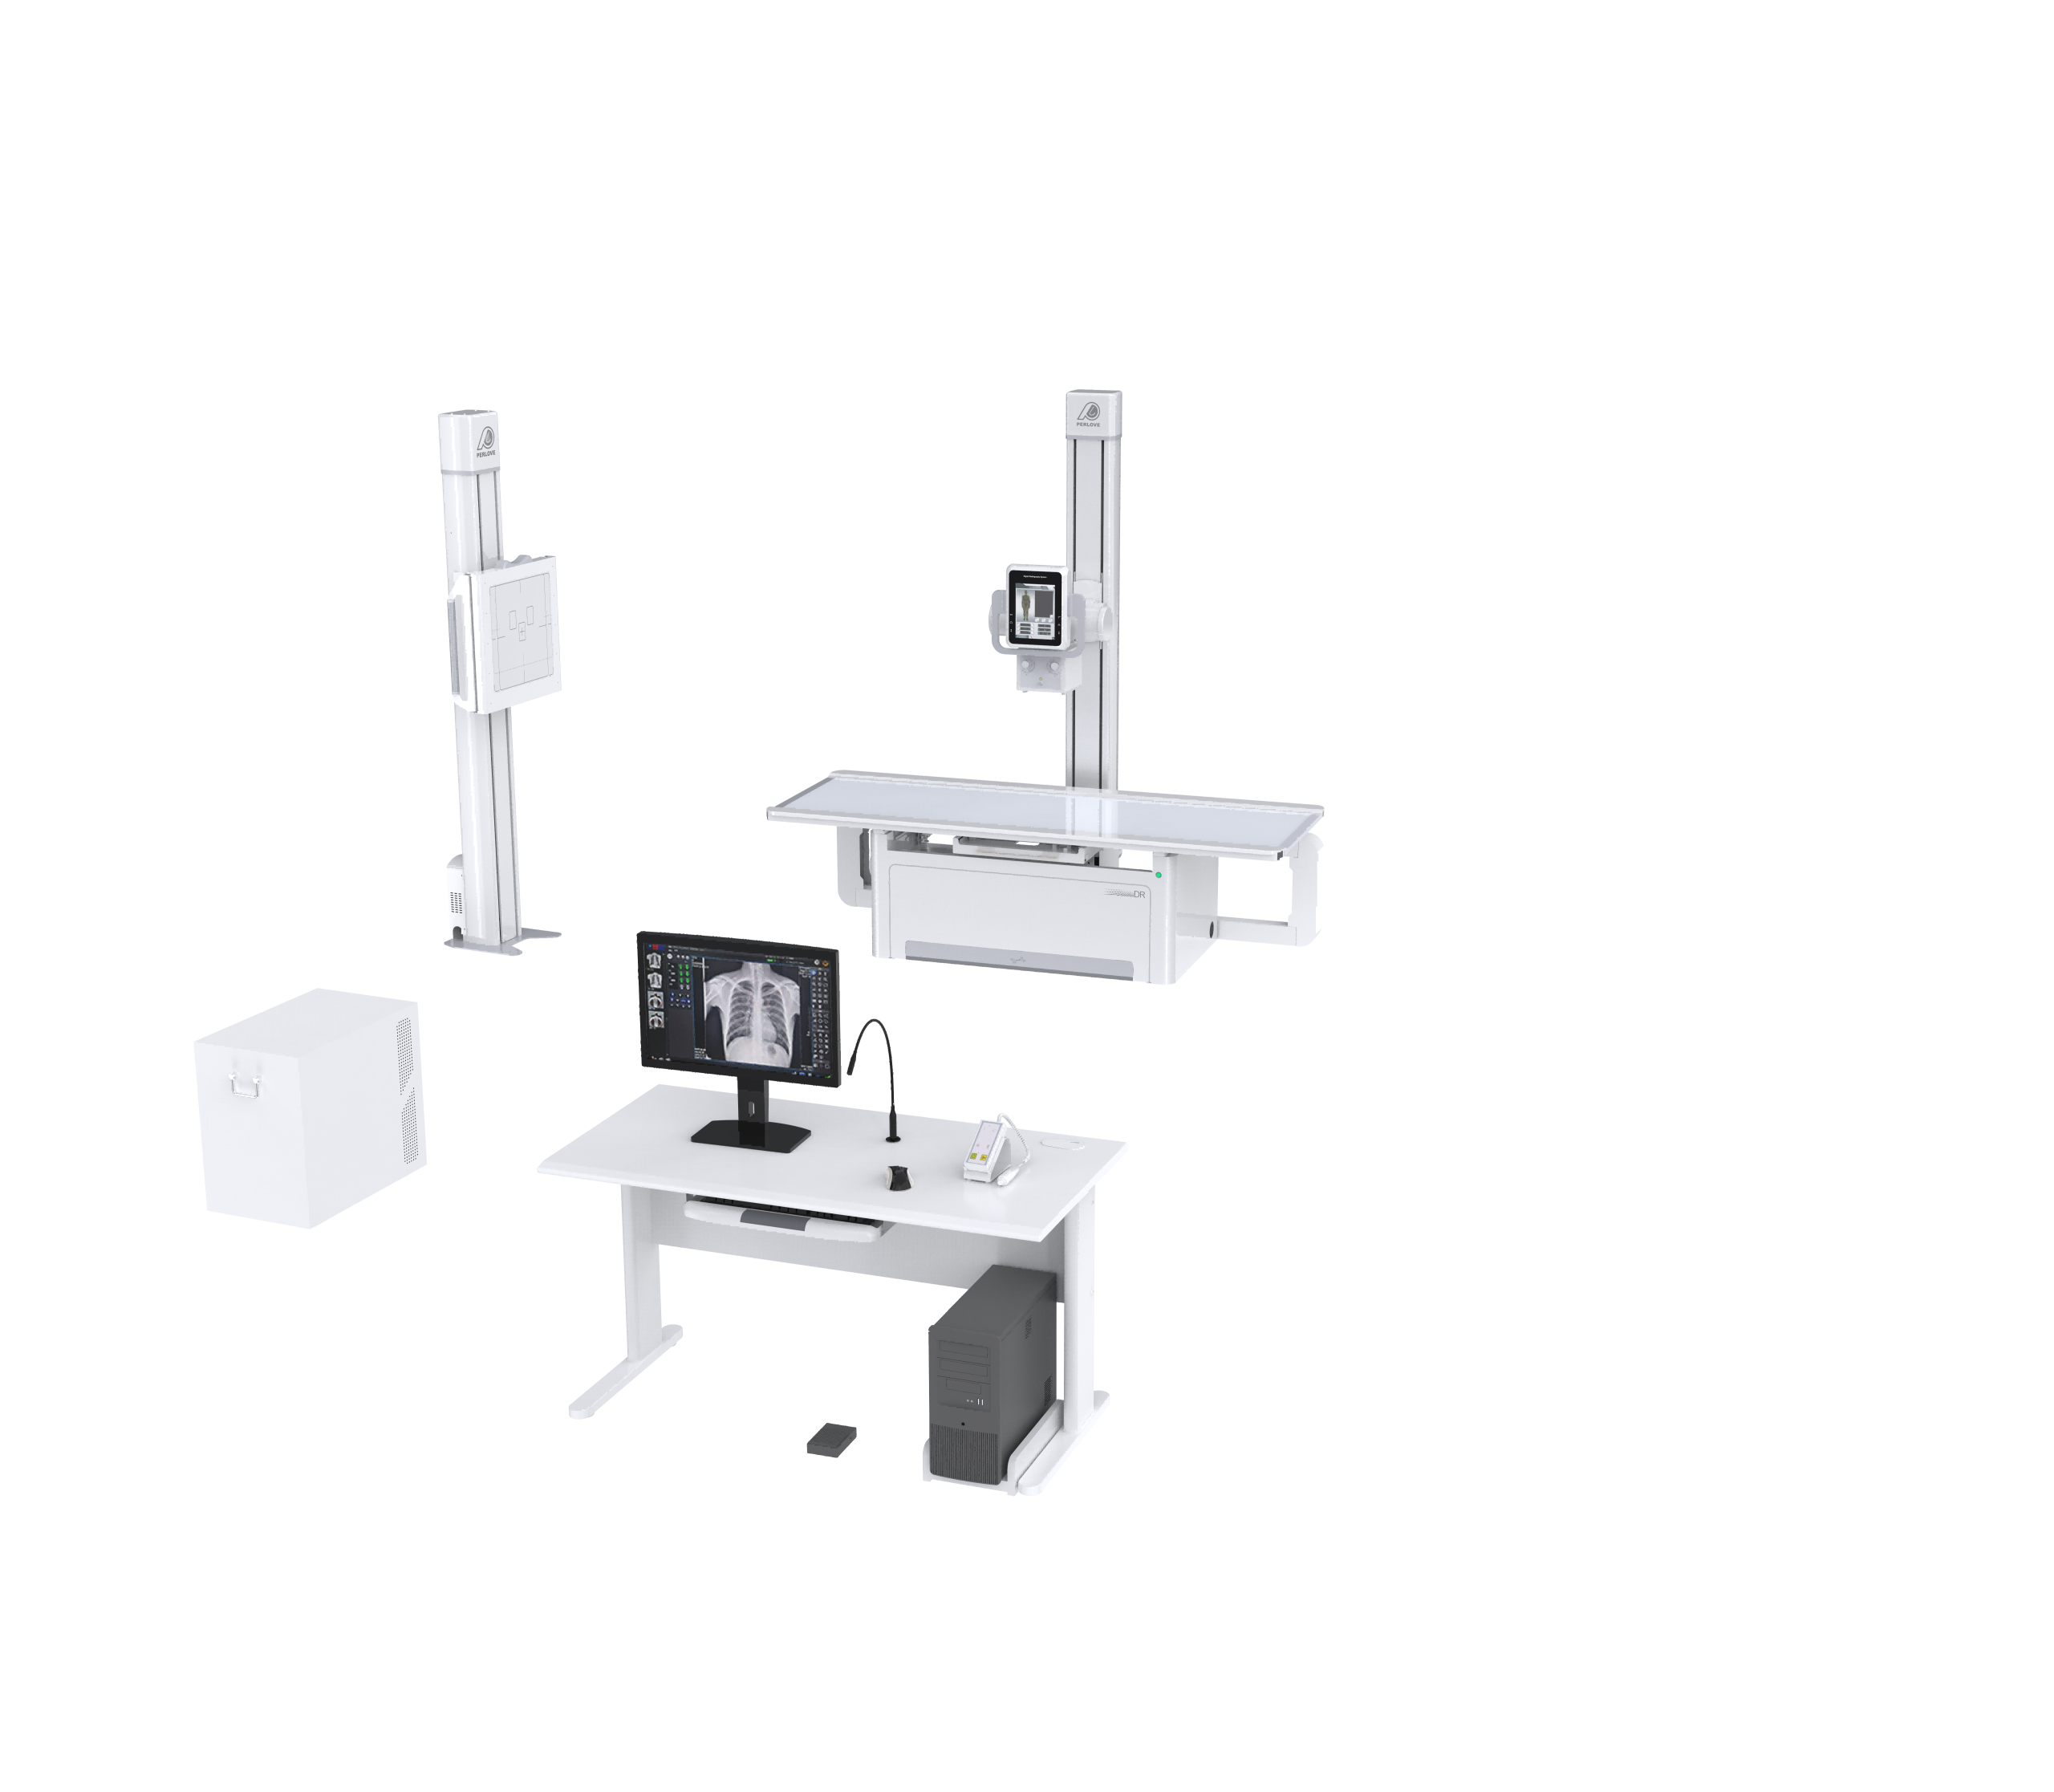

DMXR13 Digital Radiography Machine Perlove Tube Floor-Mounted X-Ray Machine For Radiology Department

Model: PSKU0140

| Product Name | DMXR13 Digital Radiography Machine Perlove Tube Floor-Mounted X-Ray Machine For Radiology Department |

| SKU | PSKU0140 |

| Size | 2120*965*450-740mm |

| Packing Size of set | 2090*1100*430mm (1 set per carton) |

| Loading capacity | 250kg / 551lbs |

1. Features:

1) Voltage: 380V±38V

2) Frequency: 50Hz±10Hz

3) Electrical Power: Three phase

4) Output Power: 50kw

5) Inverter Frequency: 500KHz

6) Tube voltage: 40kV – 150kV, 1 kv step

7) Tube current: 10mA-630mA

8) mAs: 0.1-630mAs

9) Illumination brightness: >=200Lux

10) Filiter: >=1mmAL

11) Tube Focus:big/small: 1.2mm /0.6mm

12) Input power: Big focus 74kW Small focus 30kW

13) Target surface: 12°